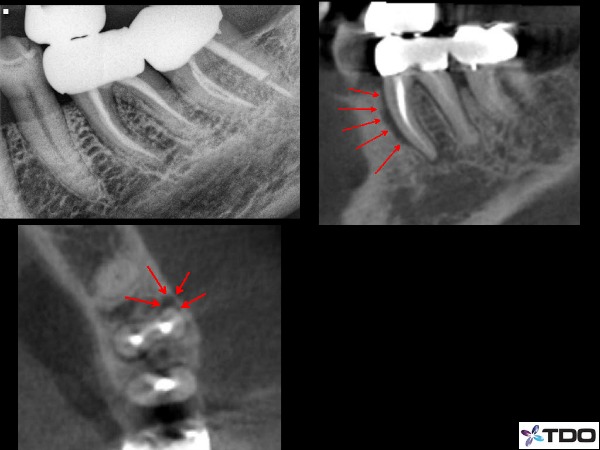

–vertical root fractures (figure 4)

Fig. 4 Clear vertical root fracture illustrated with red arrows. Note: it is rare to see radiographic confirmation of a fracture.

Now that we have CBCT imaging in the office we can use that additional and valuable tool. However, one thing to be aware is that the CBCT will rarely show a vertical fracture. Our CBCT machine will allow us to view individual slice thickness as small as 0.076mm, but most fracture lines are even smaller in width. However, it does show the bone loss patterns. We can look for vertical bone loss that is not present on the regular periapical x-ray. We can look for a narrow site of vertical bone loss (figure 8). Vertical sites of bone loss in near proximity to posts are also quite suggestive of a fractured root. Areas of radiolucency that is only present on a lateral surface vs. infections that have an apical presence with a lateral presence. These would be helpful indicators to determine if the presence of a fracture and ultimately if a tooth is savable.

Fig.8 This patient arrived with pain localized to tooth #19. The periapical radiograph does not show anything definitive. However the CBCT certainly shows a long, narrow, and localized pattern of bone loss on the MB line angle of the mesial root. This would certainly be quite suggestive of a root fracture.